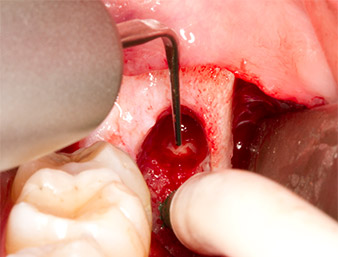

Utilizzando uno strumento per lo sbrigliamento periodontale (Piezomed P1), lo spazio del legamento periodontale della radix relicta è stato quindi ampliato minimamente (Fig. 8).

Lo stesso strumento attivato è stato inserito nel canale della radice per allentare il frammento con le vibrazioni micro-oscillatorie (Fig. 9-10).

Piezomed P1

Fig. 9: Lo strumento Piezomed P1 è consigliato dal produttore principalmente per lo sbrigliamento periodontale ma è anche adatto a scopi chirurgici. Qui lo vediamo posizionato sul canale della radice dopo un minimo ampliamento dello spazio del legamento periodontale.

Fig. 10: Grazie alla sua forma sottile, lo strumento può penetrare nel canale della radice e rimuovere il residuo di radice tramite la micro-oscillazione (vibrazione).